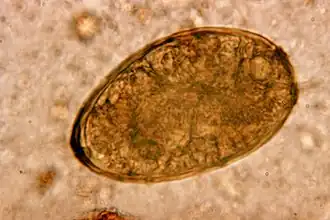

Paragonimus westermani é um verme achatado, parasita do filo Platyhelminthes classe Trematoda. É endémico na Ásia.[1]

Os caracóis do género Oncomelania os caranguejos de água doce e os suínos são essenciais no ciclo de vida deste parasita. A infecção por P. westermani é uma doença séria, denominada paragonimíase (que também pode ser causada por outras espécies do género Paragonimus), que afecta geralmente os pulmões, mas que pode afectar também o cérebro ou o abdômen.[2][3]